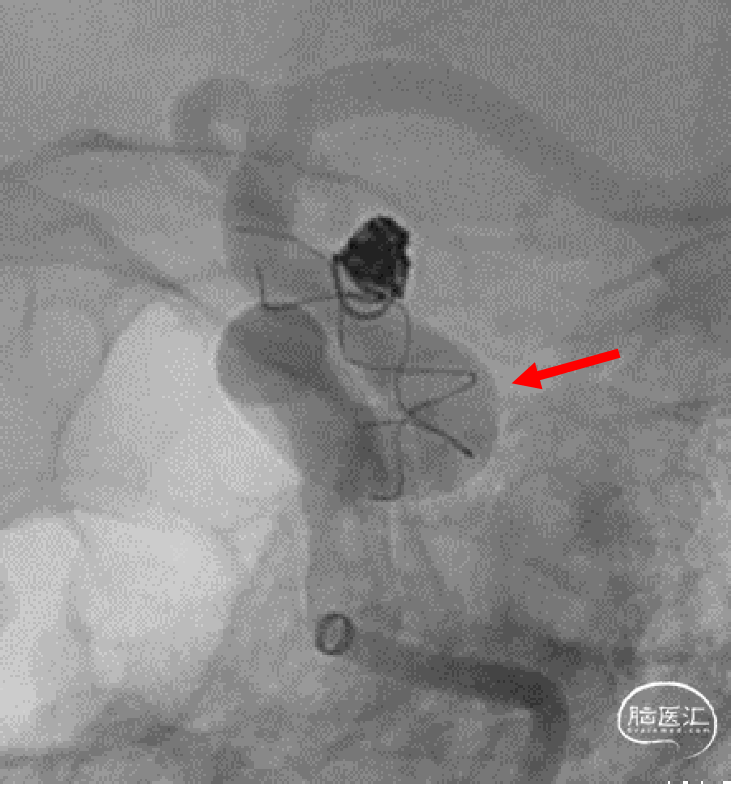

图1. a,b,c:患者为60岁女性,DSA造影显示左侧颈内动脉C6段前壁宽颈动脉瘤,高分辨MRI提示动脉瘤管壁有强化。

图2. a,b:采用支架半释放辅助栓塞宽颈动脉瘤,动脉瘤近端血管弯度较大。

图2. c,d:编织支架(LEO+3.5×25)过弯时卸张力,支架导管沿小弯侧走行,充分打开。